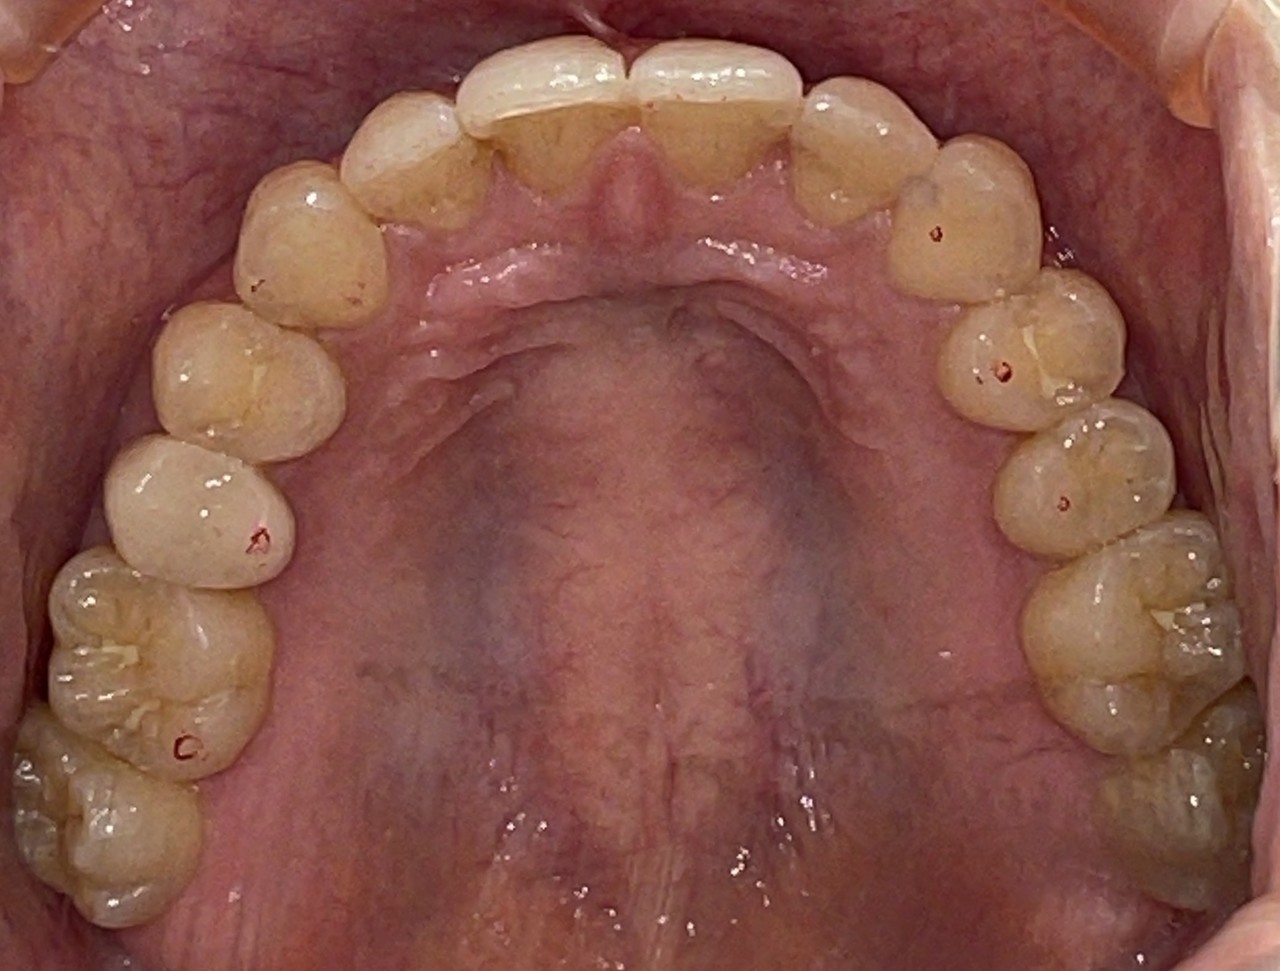

Before

After

矯正の種類 / invisalign GO

年齢・性別 / 30代女性

主訴  /  叢生、交叉咬合

治療期間 / 17ヶ月

費用 / 簡易検査 5,000円(税別) 精密検査 30,000円(税別)

両顎マウスピース 450,000円(税別) 両顎リテイナー料 60,000円(税別)

※マウスピース交換時別途調節料5,000円(税別)

副作用 / 口内炎・歯の移動に伴う痛み・知覚過敏 ※数日で収まる場合が多いです

リスク / 後戻り防止の為、夜のみマウスピースで保定を指示